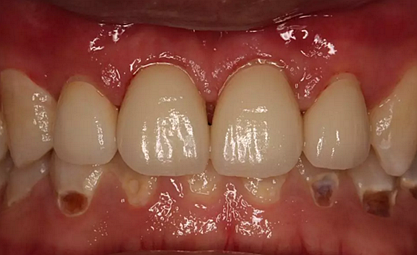

第5次復(fù)診的時候,終于讓我們4個兄弟恢復(fù)了正常的容顏。

現(xiàn)在剩下的任務(wù)就是為我其他的兄弟姐妹們治療了。需要做根管的做根管,需要做冠的做冠,需要樹脂充填的做樹脂充填。前前后后主人帶我們進行了12次的復(fù)診,歷時6個月,現(xiàn)在的我們是這樣的